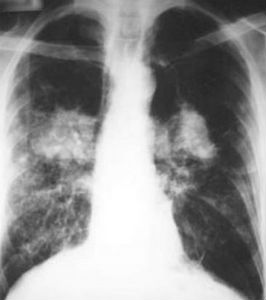

Esto es lo que ha constado una investigación realizada por científicos de la Universidad de Birmingham, en el Reino Unido, en la que se ha contrastado que los pacientes de trasplante de pulmón que reciben los pulmones de fumadores tienen una mejor supervivencia global que los que permanecen en listas de espera. Eso sí, sobreviven menos tiempo después del trasplante que aquellos que han recibido pulmones de no fumadores.

Los datos indican que los pacientes que esperan un trasplante de pulmón en el Reino Unido sobrevivirán más tiempo si están dispuestos a aceptar pulmones de cualquier donante adecuado, independientemente de los antecedentes de tabaquismo. Los investigadores usaron información del Registro de Trasplantes del Reino Unido, y la Oficina de Estadísticas Nacional, para examinar las tasas de supervivencia de 2.181 pacientes adultos del Reino Unido, en espera de trasplantes de pulmón, entre julio de 1999 y diciembre 2010.

De 1.295 trasplantes de pulmón que tuvieron lugar durante este período, en torno a 2 de cada 5 procedían de donantes con antecedentes de tabaquismo. El análisis mostró que aquellos que recibieron pulmones de fumadores tenían un 46% más de morir a los tres años del trasplante que los que recibieron pulmones de no fumadores pero, en comparación con los que se quedaron en lista de espera durante el período de estudio, la probabilidad de muerte después de la inscripción fue un 21%menor para los pacientes que recibieron pulmones de fumadores.